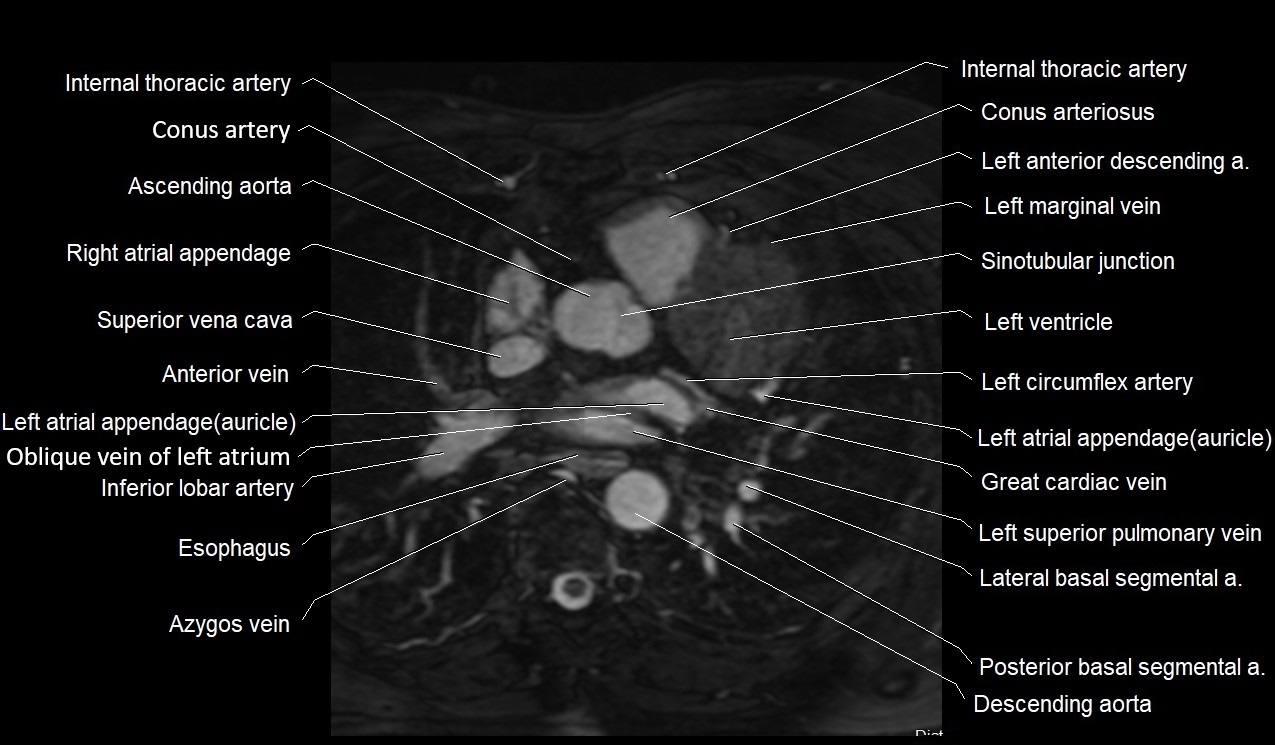

MRI image